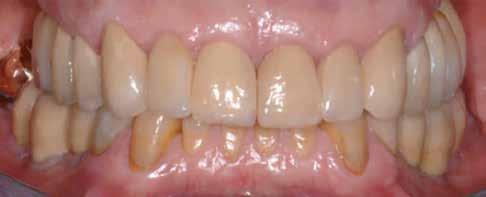

Preoperatív helyzet

Egy fiatal páciens jelentkezett nálunk, akinek eltörött a szabad véggel rendelkező hídja (1. ábra). A hiányzó, első premoláris fog esetén implantációs pótlást javasoltunk. A csontállomány értékeléséhez CBCT-vizsgálatot végeztünk, és az elemzéséhez NNT Viewert (NewTom) használtunk, és copaSKY 4×10 mm-es (bredent medical) implantátumot választottuk a fog pótlásához

1. ábra: Műtét előtti fogászati panorámafelvétel, amelyen a hiányzó felső állcsont jobb első premolárisát és a szabad véggel rendelkező hidat láthatjuk. — 2. ábra: Az implantátum méreteinek megtervezése CBCT-vel. 3. ábra: Bukkális lágyrészdefektus. — 4. ábra: A biológiai szélesség értékelése a vertikális lágyszövetvastagság alapján. 5. ábra: Palatinális „tekercslebeny” – Palatal roll flap. — 6. ábra: Bredent medical copaSKY 4x10 implantátumbeültetés. 7. ábra: Szubkresztális implantátumbeültetés a várható biológiai szélességnek megfelelően.

(2. ábra). A lágyszövetek értékelése Seibert szerinti I. osztályú csontdefektust állapított meg (3. ábra), ezért a beavatkozáskor palatinális „tekercslebenyt” preparáltunk (palatal roll flap), és implantációt végeztünk, hogy kompenzálni tudjuk a bukkális lágyszövet-behúzódást. Megmértük a vertikális lágyszövetvastagságot, és úgy terveztük, hogy a szubkresztális implantátum beültetése összhangban legyen a biológiai szélesség kialakulásával a transzgingivális gyógyulási periódus alatt (4. ábra)